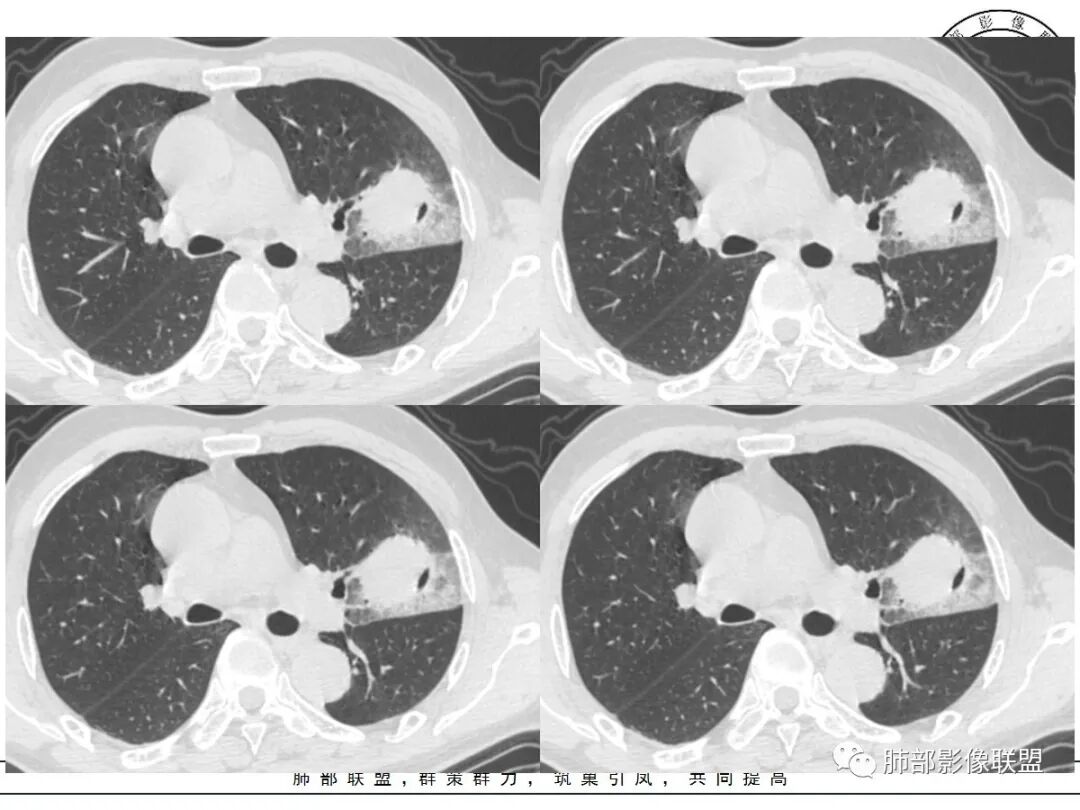

1、团片状,实行密度区外观整体圆顿,位于上叶尖后段与下舌段区间。局部膨隆,但未见分叶,肿瘤多见。

2、偏心空腔病灶,气腔略呈新月形,壁不规则,腔内结节相对密实,明显强化且不均,支持新生物而非曲菌球等。炎性空洞多有强化环。

3、病变强化较明显,其内隐约显示多发小斑片状无强化灶,可疑边界不清小灶坏死区。病灶内血管影浅淡、模糊不规则。

4、支气管改变:上舌段支气管远段延入部分稍示僵硬。尖后段见分支支气管阻塞,恶性多见。

5、周围磨玻璃,3个月后逐渐转为密实,应符合当初附壁生长为主,且逐渐向实体成分转换。

6、病变长轴平行且受限于胸膜,外围大内带小,符合外朝内发展病变。“腔内结节状明显强化”加之支气管改变有力支持新生物诊断。如此大范围边界不清的磨玻璃影让人浮想联翩。如此大范围病灶,肺门纵隔未见肿大淋巴结也让人意外。

反思,恶性膨隆,远端空洞,强化坏死不均,里面血管似乎也是增粗,边界不清,似乎有侵犯。坏死还是边界不清。